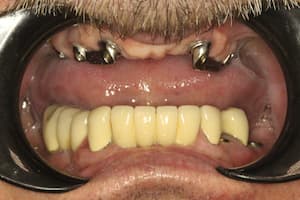

До

После

Удаление 7 зубов, установка 11 имплантов Straumann, временное и постоянное протезирование всех зубов с учетом формы, цвета и размера зубов. Работа с мягкими тканями. Импланты использовались для немедленной нагрузки.